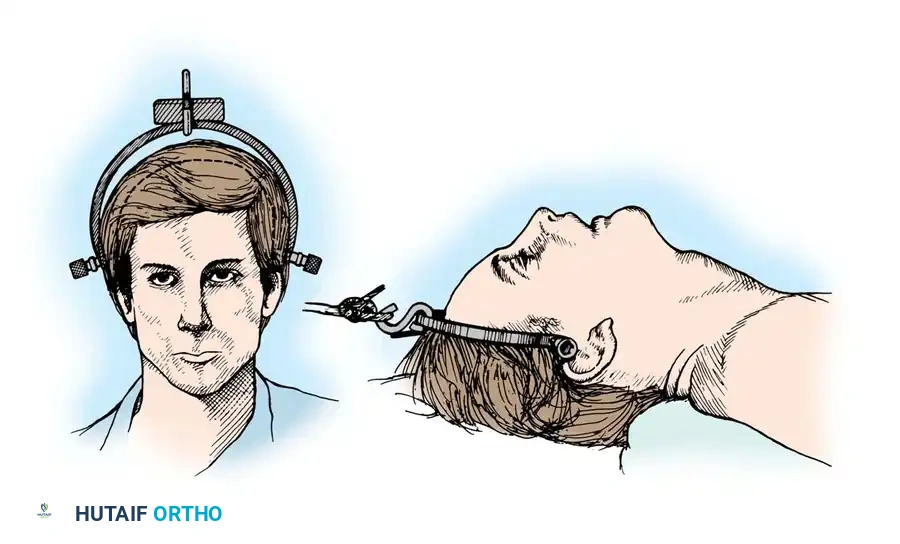

🔪 Surgical Technique 35-1: The Stretch Test Protocol

- Preparation: Apply traction through secured cranial skeletal traction (Gardner-Wells tongs). A head halter is inadequate for the weights required and risks skin necrosis. Place a rolled towel under the patient’s neck to maintain a neutral lordotic contour.

- Baseline Imaging: Place the radiographic film/detector as close to the neck as possible. Position the X-ray tube 72 inches away to minimize magnification, and obtain a baseline lateral radiograph.

- Incremental Loading: Begin with 10 lb of traction. Increase the weight in 5-lb increments.

- Monitoring: After each 5-lb addition, perform a strict neurological examination and obtain a repeat lateral radiograph.

- Viscoelastic Creep: Allow at least 5 minutes between incremental weight applications to account for the viscoelastic creep of the disrupted ligamentous structures.

- Endpoints: Continue until one of the following endpoints is reached:

- One-third of the patient's body weight is applied.

- A maximum of 65 lb is reached.

- Positive Test (STOP IMMEDIATELY): Any neurological deterioration occurs, interspace separation exceeds 1.7 mm, or the angular difference between the prestretched and loaded condition exceeds 7.5 degrees.

Closed Reduction via Skeletal Traction

After initial ATLS medical stabilization, spinal alignment is typically attempted via closed skeletal traction using spring-loaded Gardner-Wells tongs or a halo ring.

Traction Protocol:

* Apply an initial 10 lbs of weight to counteract the weight of the head.

* Add 5 lbs for each level of injury (e.g., a C5-C6 dislocation would require roughly 10 lbs + (5 levels × 5 lbs) = 35 lbs).

* Add weight in 5-lb increments with continuous clinical and radiographic monitoring.

* Maximum safe limits are generally considered to be 40 to 50 lbs, though some rigid dislocations may require more under strict fluoroscopic guidance.